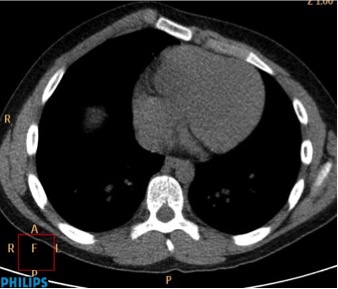

CASO: Febrícula y tos de 4 días de evolución.

Hallazgos:

- En la placa PA se observa una asimetría en los hilios pulmonares, el hilio izquierdo tiene una densidad aumentada.

- Tras examinar la placa lateral se observa un aumento de densidad en la columna que puede ser compatible con una condensación, es el signo de la desnificación vertebral.

SIGNO DE LA DENSIFICACIÓN VERTEBRAL: En la radiografía lateral normal, la densidad de la columna torácica tiende a disminuir desde la parte superior hasta el diafragma; la alteración de ese patrón por la presencia de una densidad superpuesta a la columna, indica la existencia de una consolidación pulmonar. Este signo adquiere especial valor cuando en la proyección posteroanterior la consolidación está oculta en el espacio retrocardíaco o en la base pulmonar.